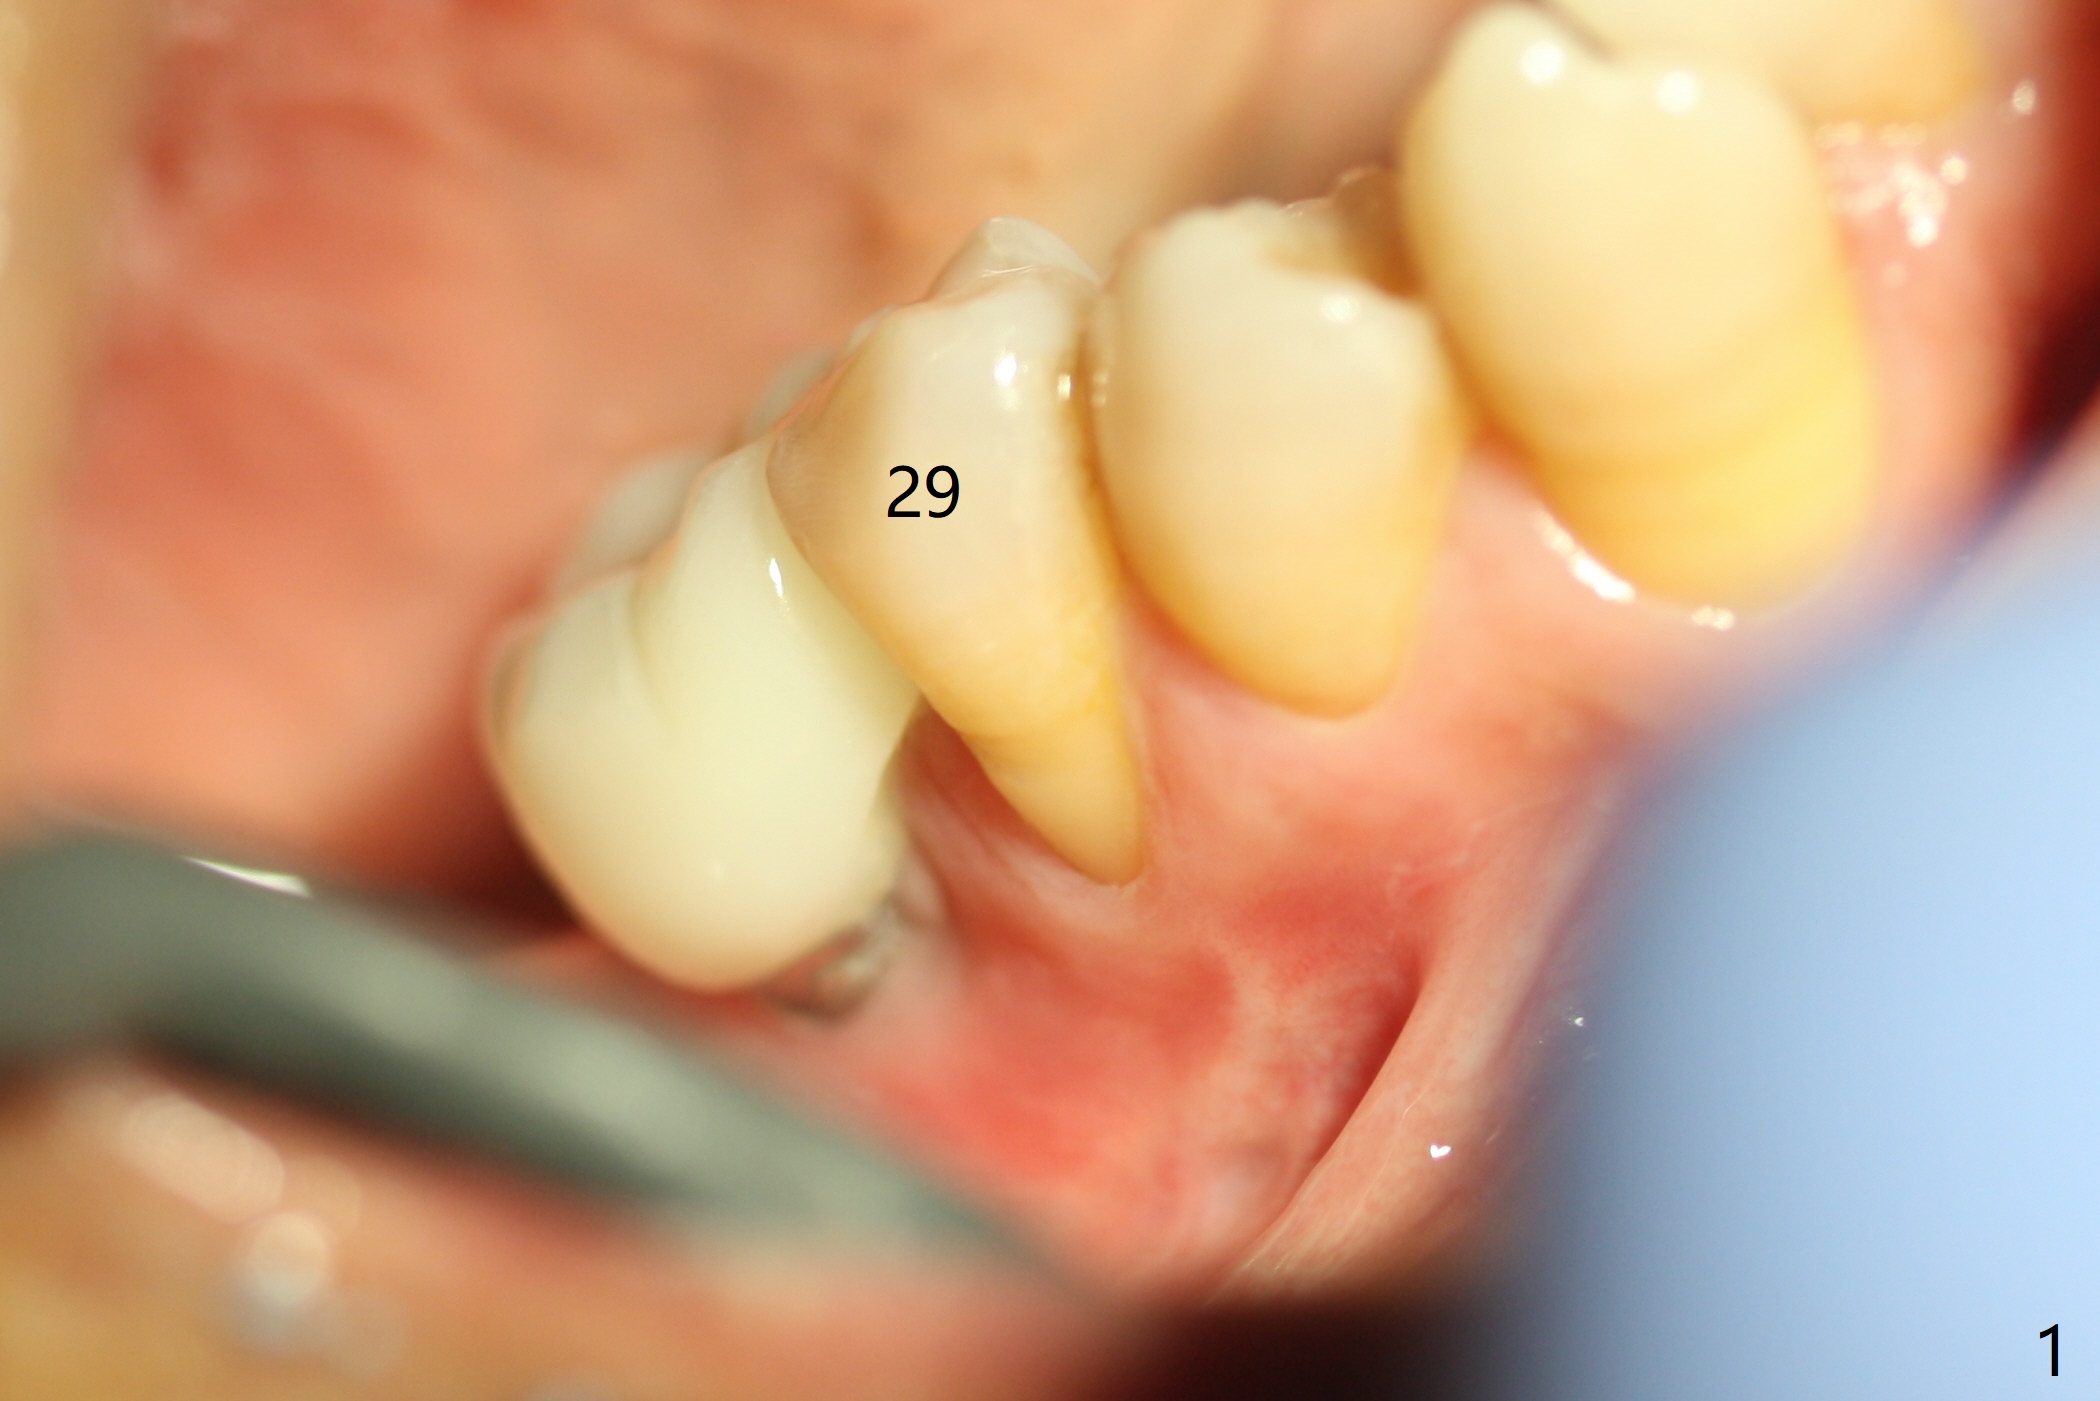

The tooth #29 has mild persistent pain radiating to the temple with mild percussion and mobility I 4.5 months post apicoectomy; the buccal recession is noticeable (Fig.1). Granulation tissue and bone graft are attached to the resected apex of the extracted tooth (Fig.2 <). The initial osteotomy with 1.5 mm drill is distal (Fig.3). After position adjustment with difficulty because of hard bone, osteotomy is finished with 2.8 and 3.2 mm Magic Drills (Fig.4). Following final drill, a 3.5x11 mm IBS implant is placed with insertion torque of 45 Ncm. With placement of a 4.5x4(4) mm abutment, Vanilla graft is placed in the buccal gap (Fig.5). Immediately postop CT shows that the implant is buccally placed (Fig.6,7 B). In fact after extraction (Fig.8), the initial osteotomy should start obliquely and as coronal and lingual as possible (Fig.9 red line). Following the initial penetration, the osteotomy should be straightened (Fig.10) so that the implant could be placed lingually (Fig11 green) to reduce buccal thread exposure. In fact there is also buccal thread exposure at #30 (Fig.12). The bone loss at #29 and 30 is minimal 4 months postop (#29, Fig.13 *)) and severe with periimplantitis at #29 one year post cementation (Fig.14). Incision will be made to exposure buccal threads of #29 and 30. If threads are within bone boundary, bone graft will be done with sticky bone after Titanium brush. If not, remove implant threads and bone graft. The worst scenario will be handled with implant removal (trephine bur 4/5 mm), either with bone graft or implant being placed lingually (IBS 3x11 mm 2-piece, to be buried, if needed (Fig.15)). Take preop photos to show #29 and 30 buccal recession and gingival erythema.